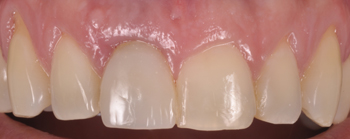

No caso clínico relatado nesta edição, o paciente apresentava sensibilidade à palpação, vermelhidão, edema e fístula na região apical do implante, e aumento progressivo da área radiolúcida apical, três meses após a colocação do implante em função (Figura 1).

Figura 2 – Aspecto clínico previamente ao tratamento cirúrgico.